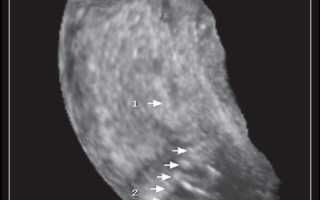

Метросальпингографические данные при двурогой матке

Наиболее достоверно характерные признаки седловидной матки обнаруживаются при проведении гистеросальпингографии: на рентгенограммах определяются 2 устья фаллопиевых труб, в области дна отчетливо читается небольшое углубление в виде седла, вдающееся в полость матки. Аналогичные признаки выявляются при проведении ЯМРТ. Гистероскопия используется для непосредственного визуального обследования полости матки. В процессе ведения беременности у пациенток с седловидной маткой осуществляется мониторинг допплерографии маточно-плацентарного кровотока, проводится кардиотокография, фонокардиография плода.